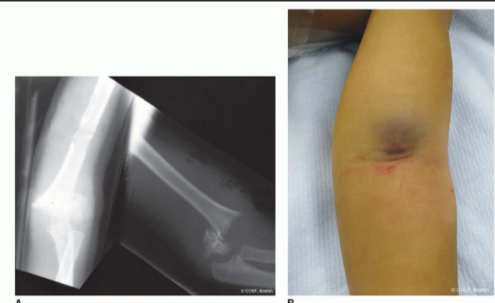

B. 关键体征: "酒窝征" (Dimple Sign)

-

• 表现: 肘前皮肤出现一个明显的凹陷或“酒窝”。 -

• 意义: 这是高危信号。它表明骨折近端的骨刺已经穿破肱肌,并很可能将正中神经和肱动脉一同卡住,并牵拉了前方的皮肤。 -

• 处理提示: 出现“酒窝征”时,单纯的闭合牵拉复位可能加重卡压,往往提示需要“反向推挤”或切开复位。 -